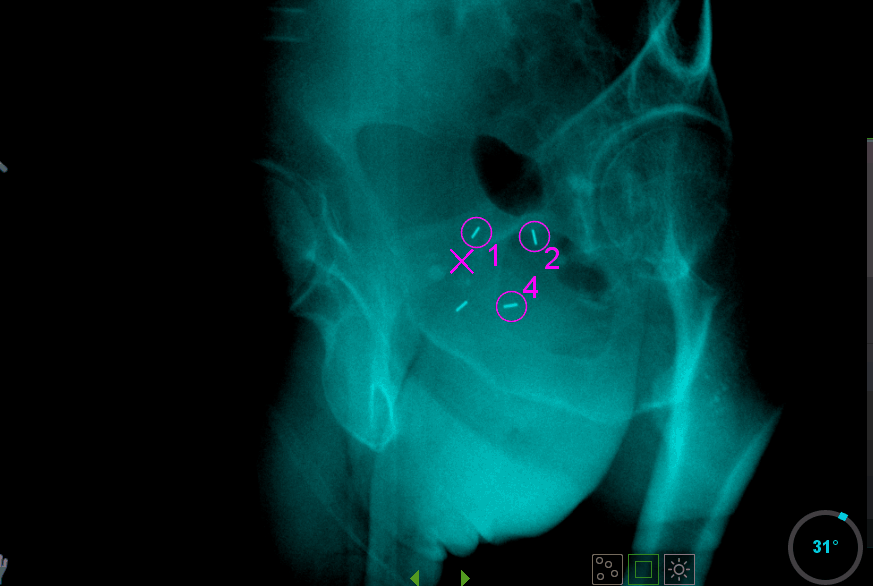

L’irradiation par stéréotaxie est asservie à la position de la prostate. Celle-ci est repérée de façon automatique par la machine de traitement avec une précision ≤ 2 mm grâce à des grains d’or implantés dans la prostate à la préparation du traitement. Ils sont détectés par l’accélérateur en utilisant de l’imagerie planaire intra-fraction.

La curiethérapie de prostate est réalisée sous anesthésie générale par implantation de grains d’iode 125 (entre 40 et 70). Ces derniers faiblement radioactifs sont implantés définitivement et irradient de façon focale la prostate durant un temps long (2 ans environ).